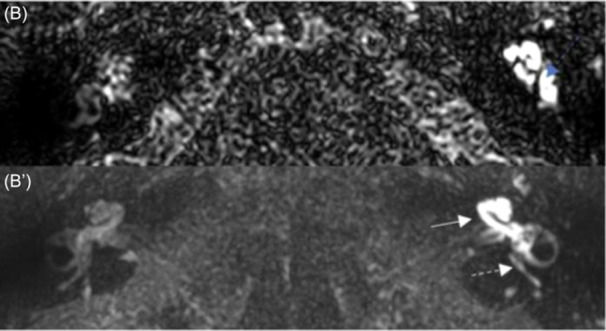

Results: A total of 712 patients underwent stapes surgery between January 2019 and December 2023. Eight patients (1.12%) were included in the study, with a median age of 52 years (interquartile range 40-54). After the surgery, seven patients presented with vertigo and sensorineural hearing loss (SNHL), and one patient presented with only vertigo with complete areflexia on caloric testing. Computed tomography (CT) of the temporal bone showed a slightly excessive penetration of the prosthesis (>1 mm) into the vestibule in one patient and a periprosthetic granuloma in another patient. CT was normal for six patients. Delayed postcontrast 3D-FLAIR MRI sequences showed blood-labyrinth barrier (BLB) impairment in the cochlea, the vestibule, and the semicircular canals in seven patients. No endolymphatic hydrops were found, but one patient presented with utricular collapse, and the saccule was not visible in three other patients.

Conclusion: Delayed postcontrast MRI sequences may reveal BLB impairment and help analyzing the endolymphatic compartment in cases of SNHL or vestibular disorders after stapes surgery. Those sequences could help uncovering the causes of such events.